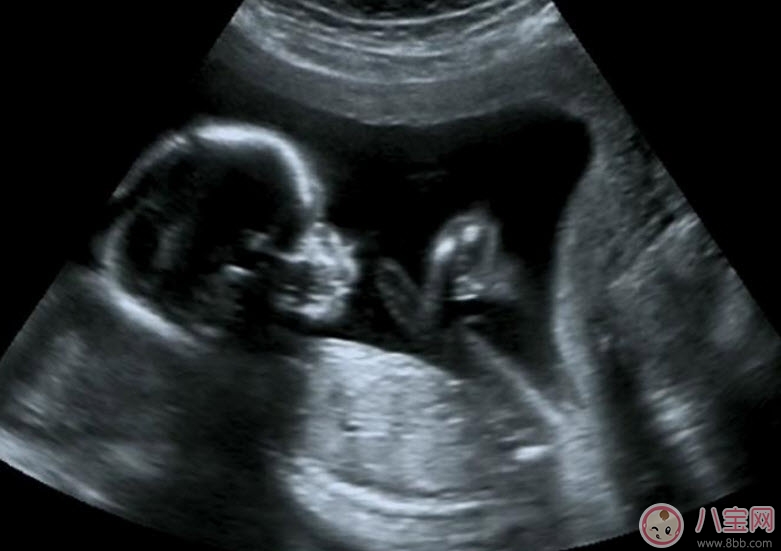

經(jīng)陰道超聲是通過超聲機上的特殊探頭而實現(xiàn)的。在陰道超聲探頭上套上薄膜,將探頭伸入陰道進行檢查。由于探頭位置接近子宮和卵巢,圖像清晰分辨率高,檢查結(jié)果較準確。除此之外,它還有另一個優(yōu)點是不需要憋尿,相對節(jié)省時間,患者感覺也好。

為監(jiān)測孕囊的部位、胎兒的生長發(fā)育情況,降低畸形兒和有缺陷兒的出生率,早孕期陰道B超檢查顯然是很必要的。早孕期做陰道B超檢查有以下幾點好處:

1.清楚地了解孕囊的位置是否正常,明確是宮內(nèi)還是宮外妊娠(俗稱宮外孕)。

2.核實孕周、判斷胚胎發(fā)育情況。根據(jù)孕囊的平均直徑、胎芽大小、胎兒的頭臀長判斷孕齡,有助于中晚孕期間判斷胎兒發(fā)育的狀況。經(jīng)陰道B超胎芽大于5mm時,應(yīng)該見到胎心搏動。如果沒有見到胎心搏動,提示有胚胎停止發(fā)育 的可能,應(yīng)定期復(fù)查。

3.判斷胚胎的數(shù)目,這是早期診斷是否多胎妊娠的最準確的方法。

4.觀察胎盤的早期發(fā)育。妊娠6周時,胚胎的葉狀絨毛膜與子宮的底蛻膜開始形成原始胎盤,妊娠8周,就可以辨認出胎盤了。

5.及早發(fā)現(xiàn)子宮、附件的異常。了解是否有子宮畸形、肌瘤以及附件區(qū)腫物等等。